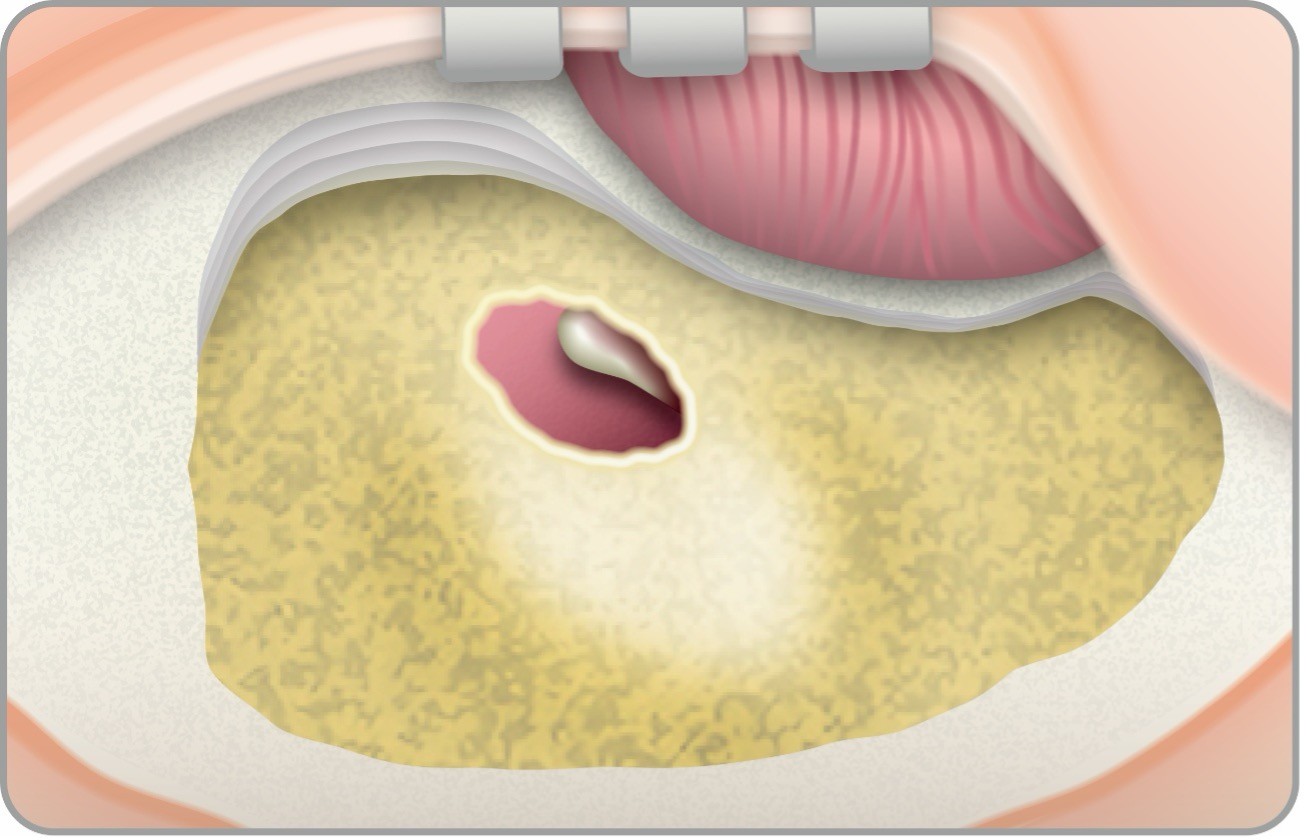

手術方法は、①耳後部の皮膚切開、②乳突削開:乳突洞および乳突蜂巣(Mastoid)の骨削開、③後鼓室開放、④人工内耳電極挿入の順に行います。②以降は通常、顕微鏡や手術用ドリルなどを使用して行われます。